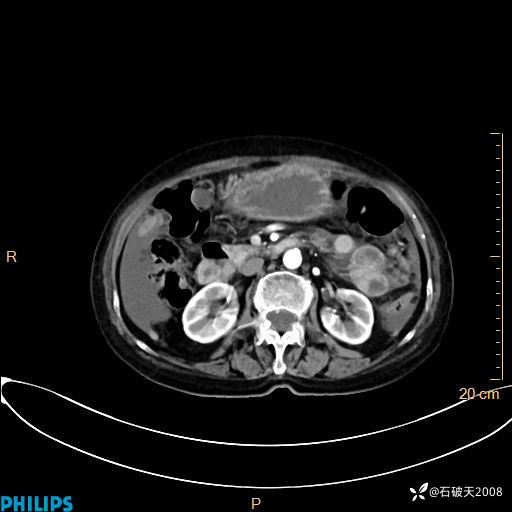

动脉期